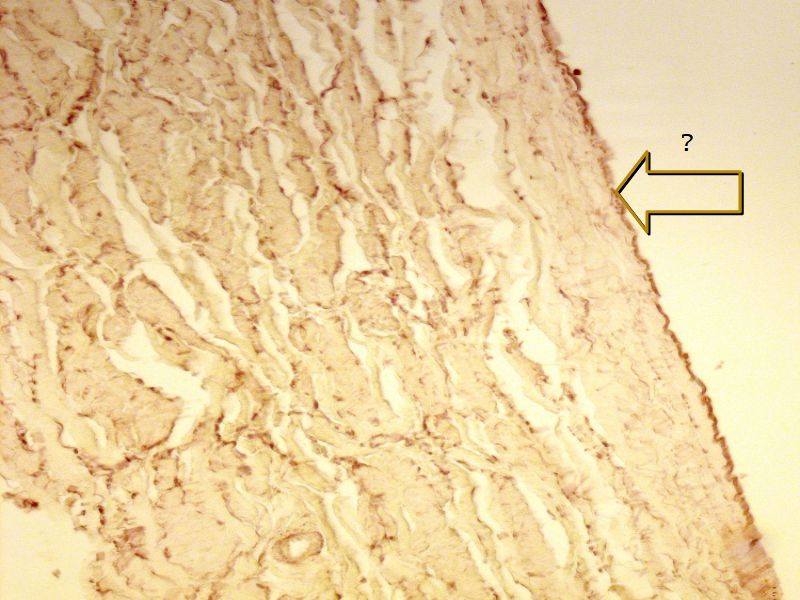

Fill in all the missing labels, and assess as you move through the slides. Answers on the down slide. It is important to do this using pen and paper, and not just glance through the images.